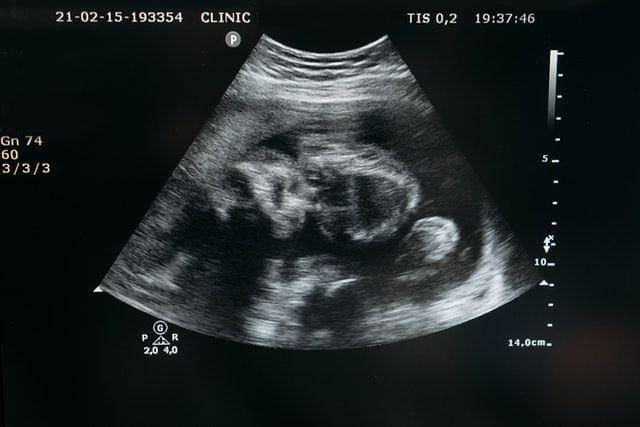

Dikutip dari nhs.uk, posisi plasenta akan diamati melalui tes ultrasound di usia kehamilan 18 hingga 21 minggu. Dokter akan mengamati posisi plasenta lagi di usia kehamilan 32 minggu, terutama bila menemukan tanda-tanda yang mengarah kepada plasenta previa di tes sebelumnya. Operasi sesar akan dilakukan apabila kondisi tidak membaik guna mencegah pendarahan.